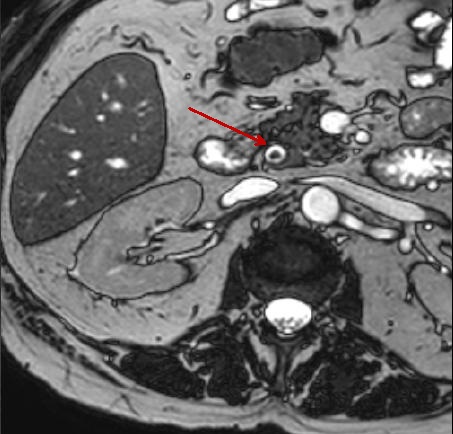

Une autre calcul choledocien

( fleche rouge ) en aspect radiologioque ovalaire hypointense |